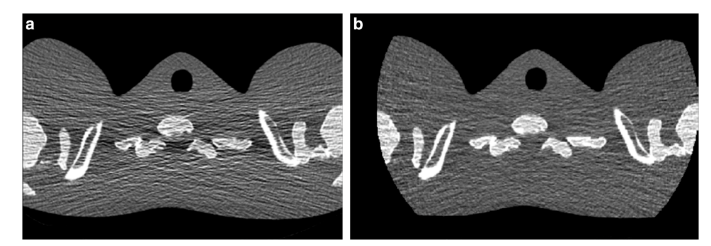

在低剂量检查中,EID产生的电子噪声会在重建图像中转化为条纹伪影和CT值不稳定性。电子噪声和相关伪影的存在限制了在肺癌筛查等低剂量检查中使用EID-CT系统所能达到的剂量降低程度。在PCD中可以通过能量阈值消除电子噪声的影响。

当最低能量阈值被设定为高于低幅电子噪声水平时,真实的X射线计数就能从电子噪声中分离出来(图2,顶部),从而减少伪影,并在较低辐射剂量下提高CT值的稳定性(图3)。

图3 在低光子通量条件下通过EID(a)和PCD(b)原型获得的拟人肩部模型图像。与EID图像相比,PCD图像的水平条纹伪影明显减少,整体外观更加均匀。